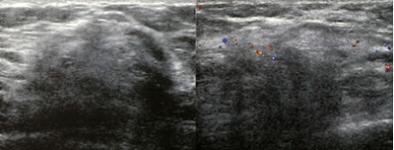

- The predominance of mesenchyme in the diffusely infiltrating breast malignancy:

- Allows it to be imaged with greater sensitivity by ultrasound than by mammography:

- The thin sheets or veils of tissue reflect the ultrasound waves:

- But are relatively easily penetrated by x-rays

- The hypoechoic changes can also usually be seen on hand held ultrasound, Image: